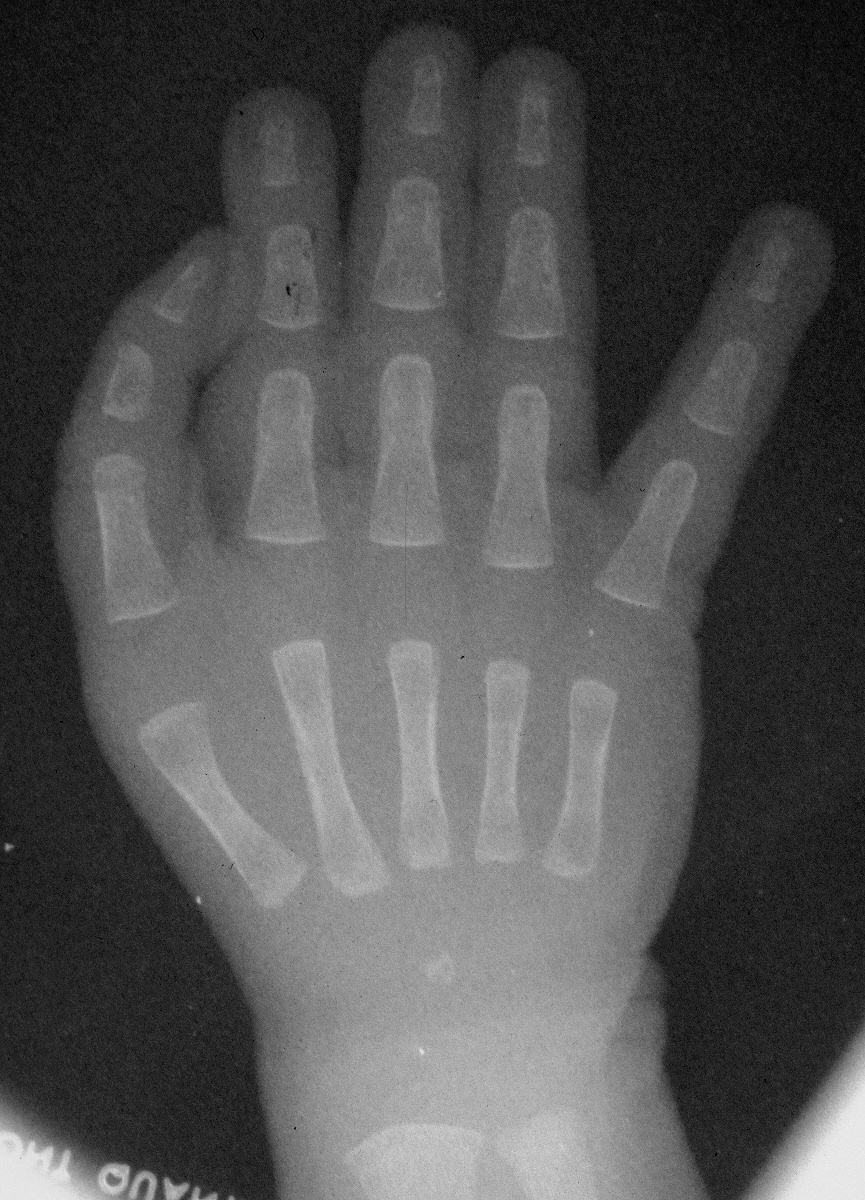

| Immediately

postop. |

| Immediately preop. |